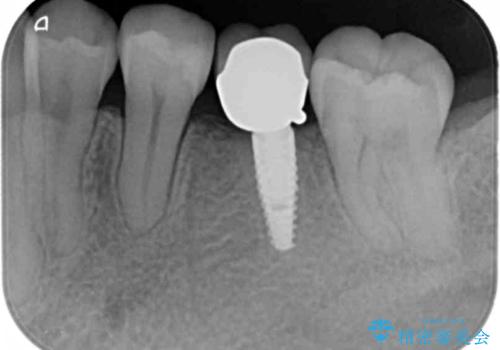

- 下の奥の銀歯を白くしたいとのことで来院されました。

セラミックインレーでの治療を行いました。

- 左下5 セラミックインレー 77,000円費用は治療当時の料金となります

銀の詰め物のやり替えは2回の来院で終わらせることができます。

下の歯は口を開けたときに外からよく見えるため、セラミックにやり替えることで印象が大きく変わります。